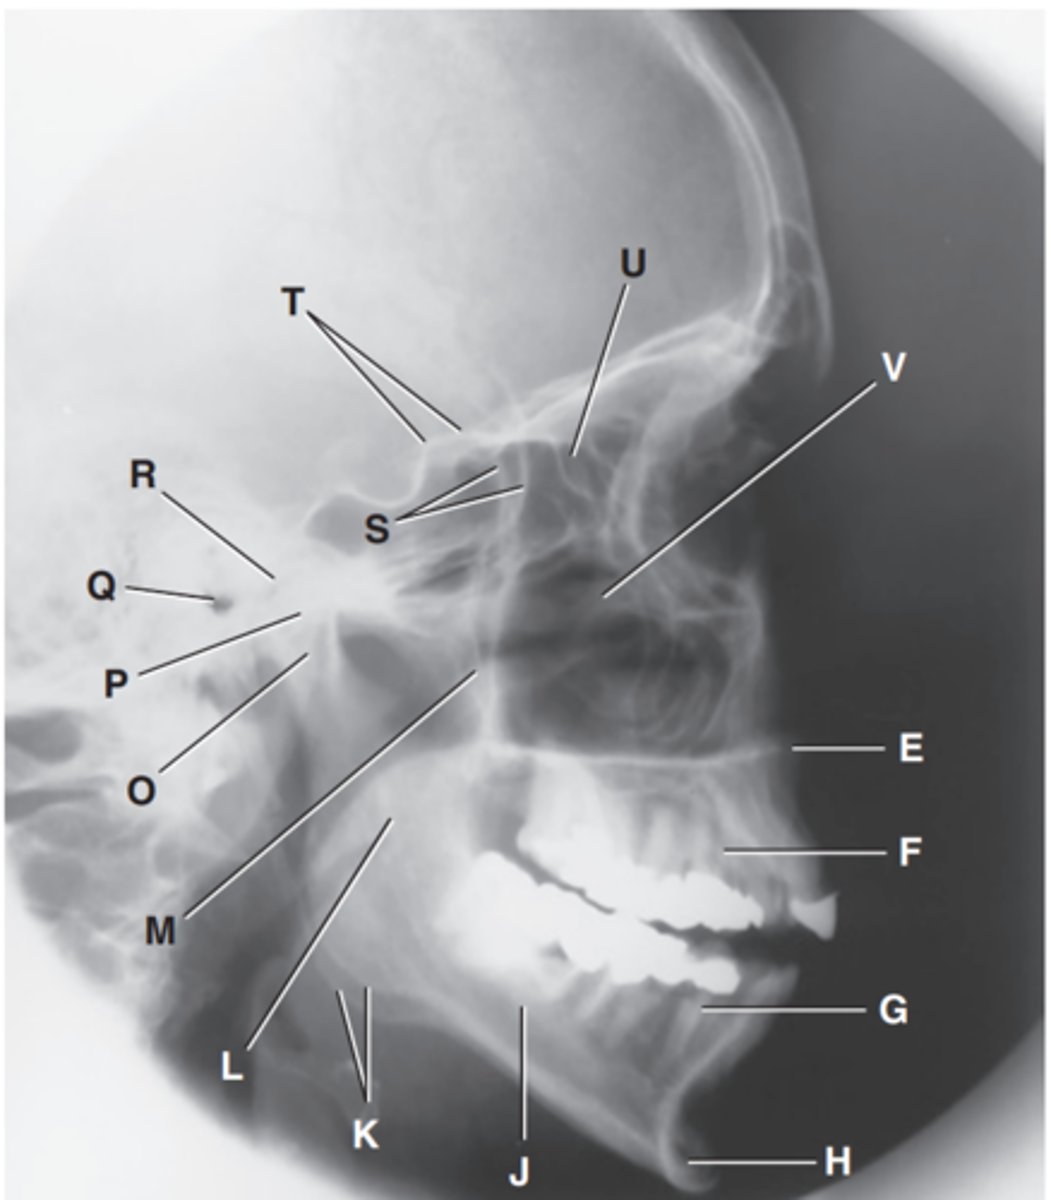

Zygomatic arch

Label A

Right zygomatic bone

Label B

Right nasal bone

Label C

Frontal process of right maxilla

Label D

Anterior nasal spine

Label E

Alveolar process of maxilla

Label F

Alveolar process of mandible

Label G

Mentum or mental protuberance

Label H

Mental foramen

Label I

Body of mandible

Label J

Angle (gonion)

Label K

Ramus of mandible

Label L

Coronoid process

Label M

Mandibular notch

Label N

Neck of mandibular condyle

Label o

Condyle or head of mandible

Label P

EAM

Label Q

TM fossa of temporal bone

Label R

Greater wings of sphenoid

Label S

Lesser wings of sphenoid with anterior clinoid processes

Label T

Ethmoid sinuses between orbits

Label U

Body of maxilla containing maxillary sunuses

Label V